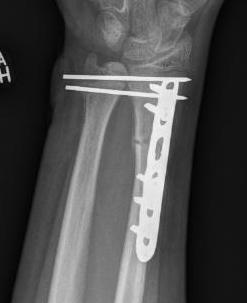

Galeazzi fracture

Galeazzi fracture with DRUJ disruption

Incidence of DRUJ instability after radius ORIF

Rettig et al J Hand Surg Am 2001

- 40 patients with Galeazzi fracture dislocations

- DRUJ instability after radius ORIF

- Type 1: radius fracture < 7.5 cm to articular surface: 55% DRUJ instability

- TYpe II: radius fracture > 7.5 cm to articular surface: 6% DRUJ instability